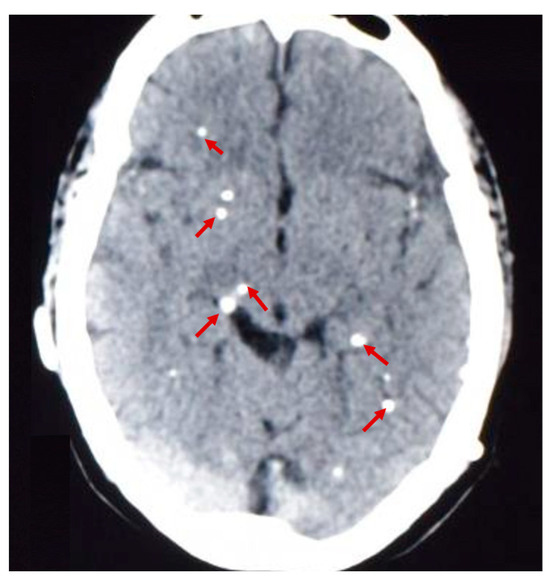

From January 2012 to July 2022, patients aged 12 years and older with brain calcifications demonstrated on non-contrast CT (Figure 1) seen at the Cysticercosis Unit of the INCN were invited to participate in this study. A cutoff of 12 years was chosen since it has been shown that calcified NCC in disease-endemic communities affects children less often than adults [33,34]. Also, there is a high probability that seizures in children could be related to primary or idiopathic generalized episodes. We adapted the diagnostic criteria defined by Del Brutto (patients from endemic T. solium areas, with or without symptoms, and with lesions compatible with calcified NCC on CT) [35]. Calcified lesions were classified as NCC-related according to a typical appearance, pattern, and location. On CT scan, calcified lesions were identified as small, clearly demarcated, hyperdense rounded nodules or punctate lesions, with or without perilesional edema [36,37]. Patients received full information about the study through a detailed informed consent process by a study physician. Exclusion criteria included: presence of viable and/or degenerating CNS cysts located at the brain parenchyma, subarachnoid space, or within the ventricular system visualized on neuroimaging; a positive ratio >10 on Ag-ELISA (highly suggestive of viable infection); having primary generalized seizures; evidence of intracranial hypertension; or focal neurological deficits. In addition, pregnant women were not included in the study. Also, participants with calcifications in physiologic conditions such as the falx or choroid plexus were excluded from the calcified NCC group, as well as participants with calcification-patterns consistent with other known diseases such as Fahr disease and arterial atherosclerosis, or a vascular malformation [37].

Figure 1.

Calcified lesions (red arrows) seen in the brain parenchyma of a patient with NCC on non-contrast CT.